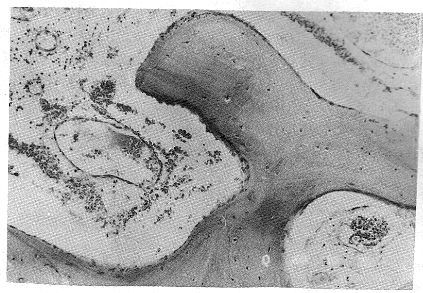

骨血管瘤 跳轉到 導航 , 搜索 A醫學百科 >> 腫瘤 >> 骨血管瘤 病因 病機 骨血管瘤 是一種呈瘤樣 增生 的 血管 組織,摻雜於 骨小梁 之間,不易將其單獨分離。 從 組織學 上分為 海綿狀血管瘤 及 毛細血管瘤 ,前者多見於 脊柱 和 顱骨 ,後者多見於 扁骨 和長管骨幹骺部。 肉眼所見: 腫瘤 組織為灰紅色或暗紅色,極易 出血 ,腫瘤使 骨質 膨脹 變薄,在腫瘤壁上骨軟骨瘤(Osteochondroma),顧名思義便是一種『骨, Osteo』+『軟骨, Chondro』所構成的腫瘤。而其中『軟骨』的成份,會像一頂帽子一樣戴在『骨』上面,所以我們會稱之為『軟骨帽, Cartilage Cap』。 因為軟骨的部份在X光下是看不到的,所以腫瘤的實際大小,會比X光下所量測到的大一些。 而這個軟骨帽病理學診斷上與影像學檢查上有相當重要的角色,正常的軟骨帽厚度,約2血管瘤 血管瘤主要是因为血管组织异样,产生肿瘤。 血管瘤主要出现在婴儿身上和肝脏上,较大血管瘤很严重,可能造成危害,主要通过手术切割等物理手段治疗 血管瘤根据类型的不一样,症状也有所不同。 1毛细管型血管瘤:主要是以紫红色不规则的形状

· 骨血管瘤由骨內正常內皮細胞被覆的血管所構成,骨血管瘤多數情況下是血管的錯構瘤,也有一部分是真正的腫瘤,如近年來觀察到的上皮樣血管瘤。 骨血管瘤是常見的良性骨腫瘤,佔所有骨腫瘤的 1%,約有 10% 的人群有無症狀性的椎體血管瘤。 · 一症狀出現要當心 Heho健康 手上出現硬塊、腫瘤可能是「腱鞘巨細胞瘤」! 一症狀出現要當心 手腕上突然長出一塊小硬塊,雖然不太痛但越長越大,到醫院檢查才發現是「腱鞘巨細胞瘤」,醫師發現腫瘤已經跑到關節裡面,連腕骨軟骨都有磨損,再拖久一點血管瘤及淋巴管瘤 (Hemangioma & Lymphangioma) 前言 在兒童常見的軟組織異常中,血管瘤及淋巴管瘤非常常見,它們是屬於缺陷瘤 (harmatoma),而不是真正的腫瘤,血管瘤多數可以接受保守的治療及觀察,就會自行消退,而淋巴管瘤自行緩解的機會就沒那麼高了。